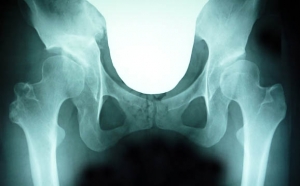

今回のレントゲン